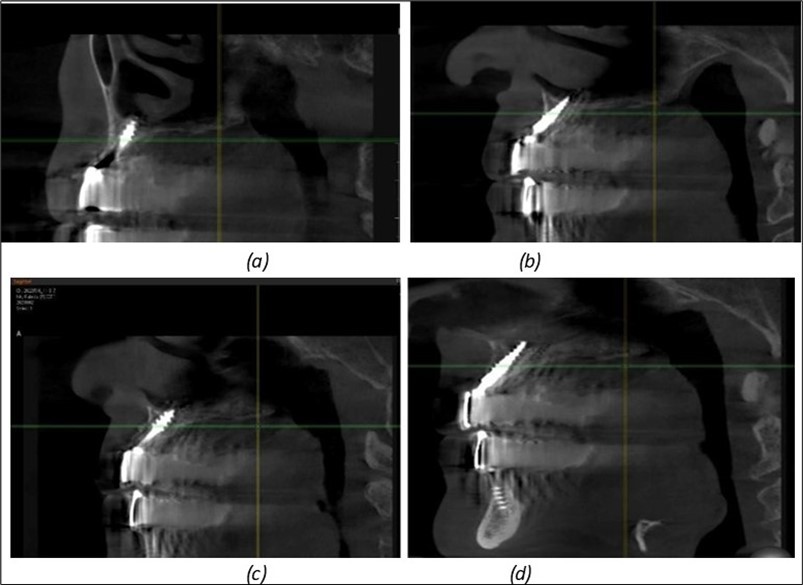

Figure 8.(a), (b) Sinus lift and grafting area with two stage implants before their removal. (c) area of fixation of BCS and TPG implants, avoiding the sinus lift and grafting area

Figure 10.Implants in the palatal sinus cortical area to avoid bone grafting: (a) BCS implant partially fixed in the graft material mass, partially in the palatal cortex; (b) Implant fixed in the palatal cortex at the junction with the nasal cortex, behind the graft material mass.

Figure 11.Implants in the anterior area anchored in the nasal cortex (BCS and TPG): (a), (c) – BCS implants fixed in the nasal cortex; (b), (d) – TPG implants fixed in the second nasal cortex with compression in the trabecular area.

Figure 12.Implants fixed distally in quadrant 4 with fixation at the level of the mylohyoid line: (a) The most distal implant fixed in unaffected bone from the previous restoration; (b) The implant fixed in the area where the two stage implant was removed.